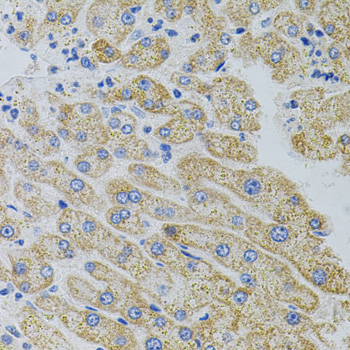

Immunohistochemistry - CRHR2 Polyclonal Antibody

Immunohistochemistry of paraffin-embedded rat kidney using CRHR2 antibody (40x lens).